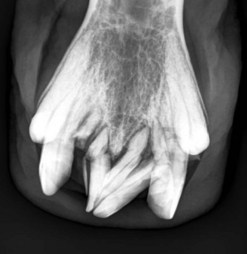

image image image

Fig. 13.37 (A) Maxillary cheek tooth row of a miniature Shetland pony with marked dysplasia of the 109, 110, and 111 and a corresponding wave mouth on the mandibular row. (B) Markedly enlarged, radiodense, dysplastic 110, which has displaced the reserve crowns and apices of 111 and 109 caudally and rostrally, respectively. (C) Abnormally small 302. The deciduous 702 remnant is retained (arrow).